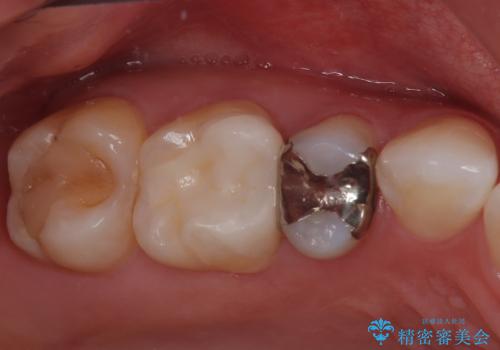

詰め物が外れかけてるのでやり替えたい セラミックインレー修復・フルジルコニアクラウン